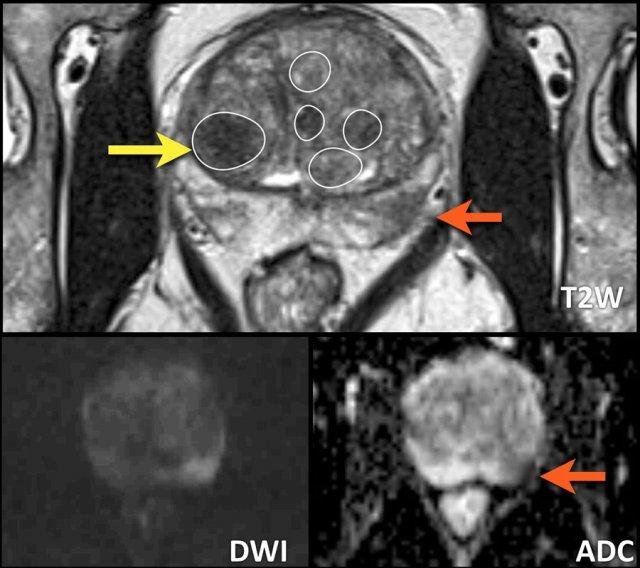

Hình ảnh

Ảnh chuỗi xung T2W mặt phẳng coronal này cho thấy nhiều loại nốt BPH khác nhau.

- Nốt tuyến (vòng tròn xanh dương)

- Nốt không điển hình (vòng tròn vàng)

- Nốt trong nốt (nhiều nốt nhỏ hơn nằm bên trong một nốt lớn hơn) (vòng tròn xanh lá).

Các nốt BPH chủ yếu là tuyến và teo nang biểu hiện tăng tín hiệu T2 mức độ vừa đến rõ, và được phân biệt với các khối u ác tính dựa vào tín hiệu và vỏ bao của chúng.

Một số nốt này có mô đệm đặc với tín hiệu thấp trên chuỗi xung T2W và ADC thấp (mũi tên vàng).

Đặc điểm quan trọng nhất để phân biệt các nốt BPH với ác tính là hình thái thường có bờ rõ và giới hạn rõ ràng, được đánh giá trên các chuỗi ảnh axial, coronal và sagittal.

Tổn thương vùng ngoại vi bên trái được phân loại PI-RADS 5 (mũi tên đỏ).

Sinh thiết có hướng dẫn MRI cho thấy Gleason 3+4.